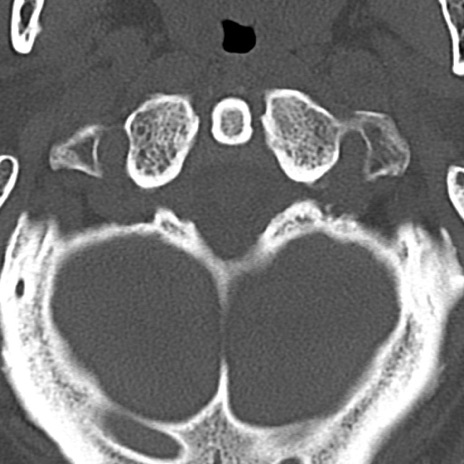

頚椎CT

横断像